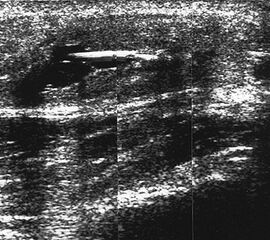

Hämarthros mit Binnenechos

Abbildung 6

Lagerung: Rückenlage.

Schnittebene: Ventraler LS über dem OSG.

Referenzstrukturen: Distale Tibia und Talusrolle, darüber Gelenkkapsel. Befunde: Echoarme Vorwölbung der Gelenkkapsel durch Hämarthros (Abb.6), gelegentlich Spiegelbildung durch Abscheidung von flüssigen und korpuskulären Anteilen. Nach dem zweiten Tag zunehmend echogener und teilweise mit fokalen Verdichtungen durch Thrombosierung. Dekompressionstest zur Abklärung der Punktionsfähigkeit.